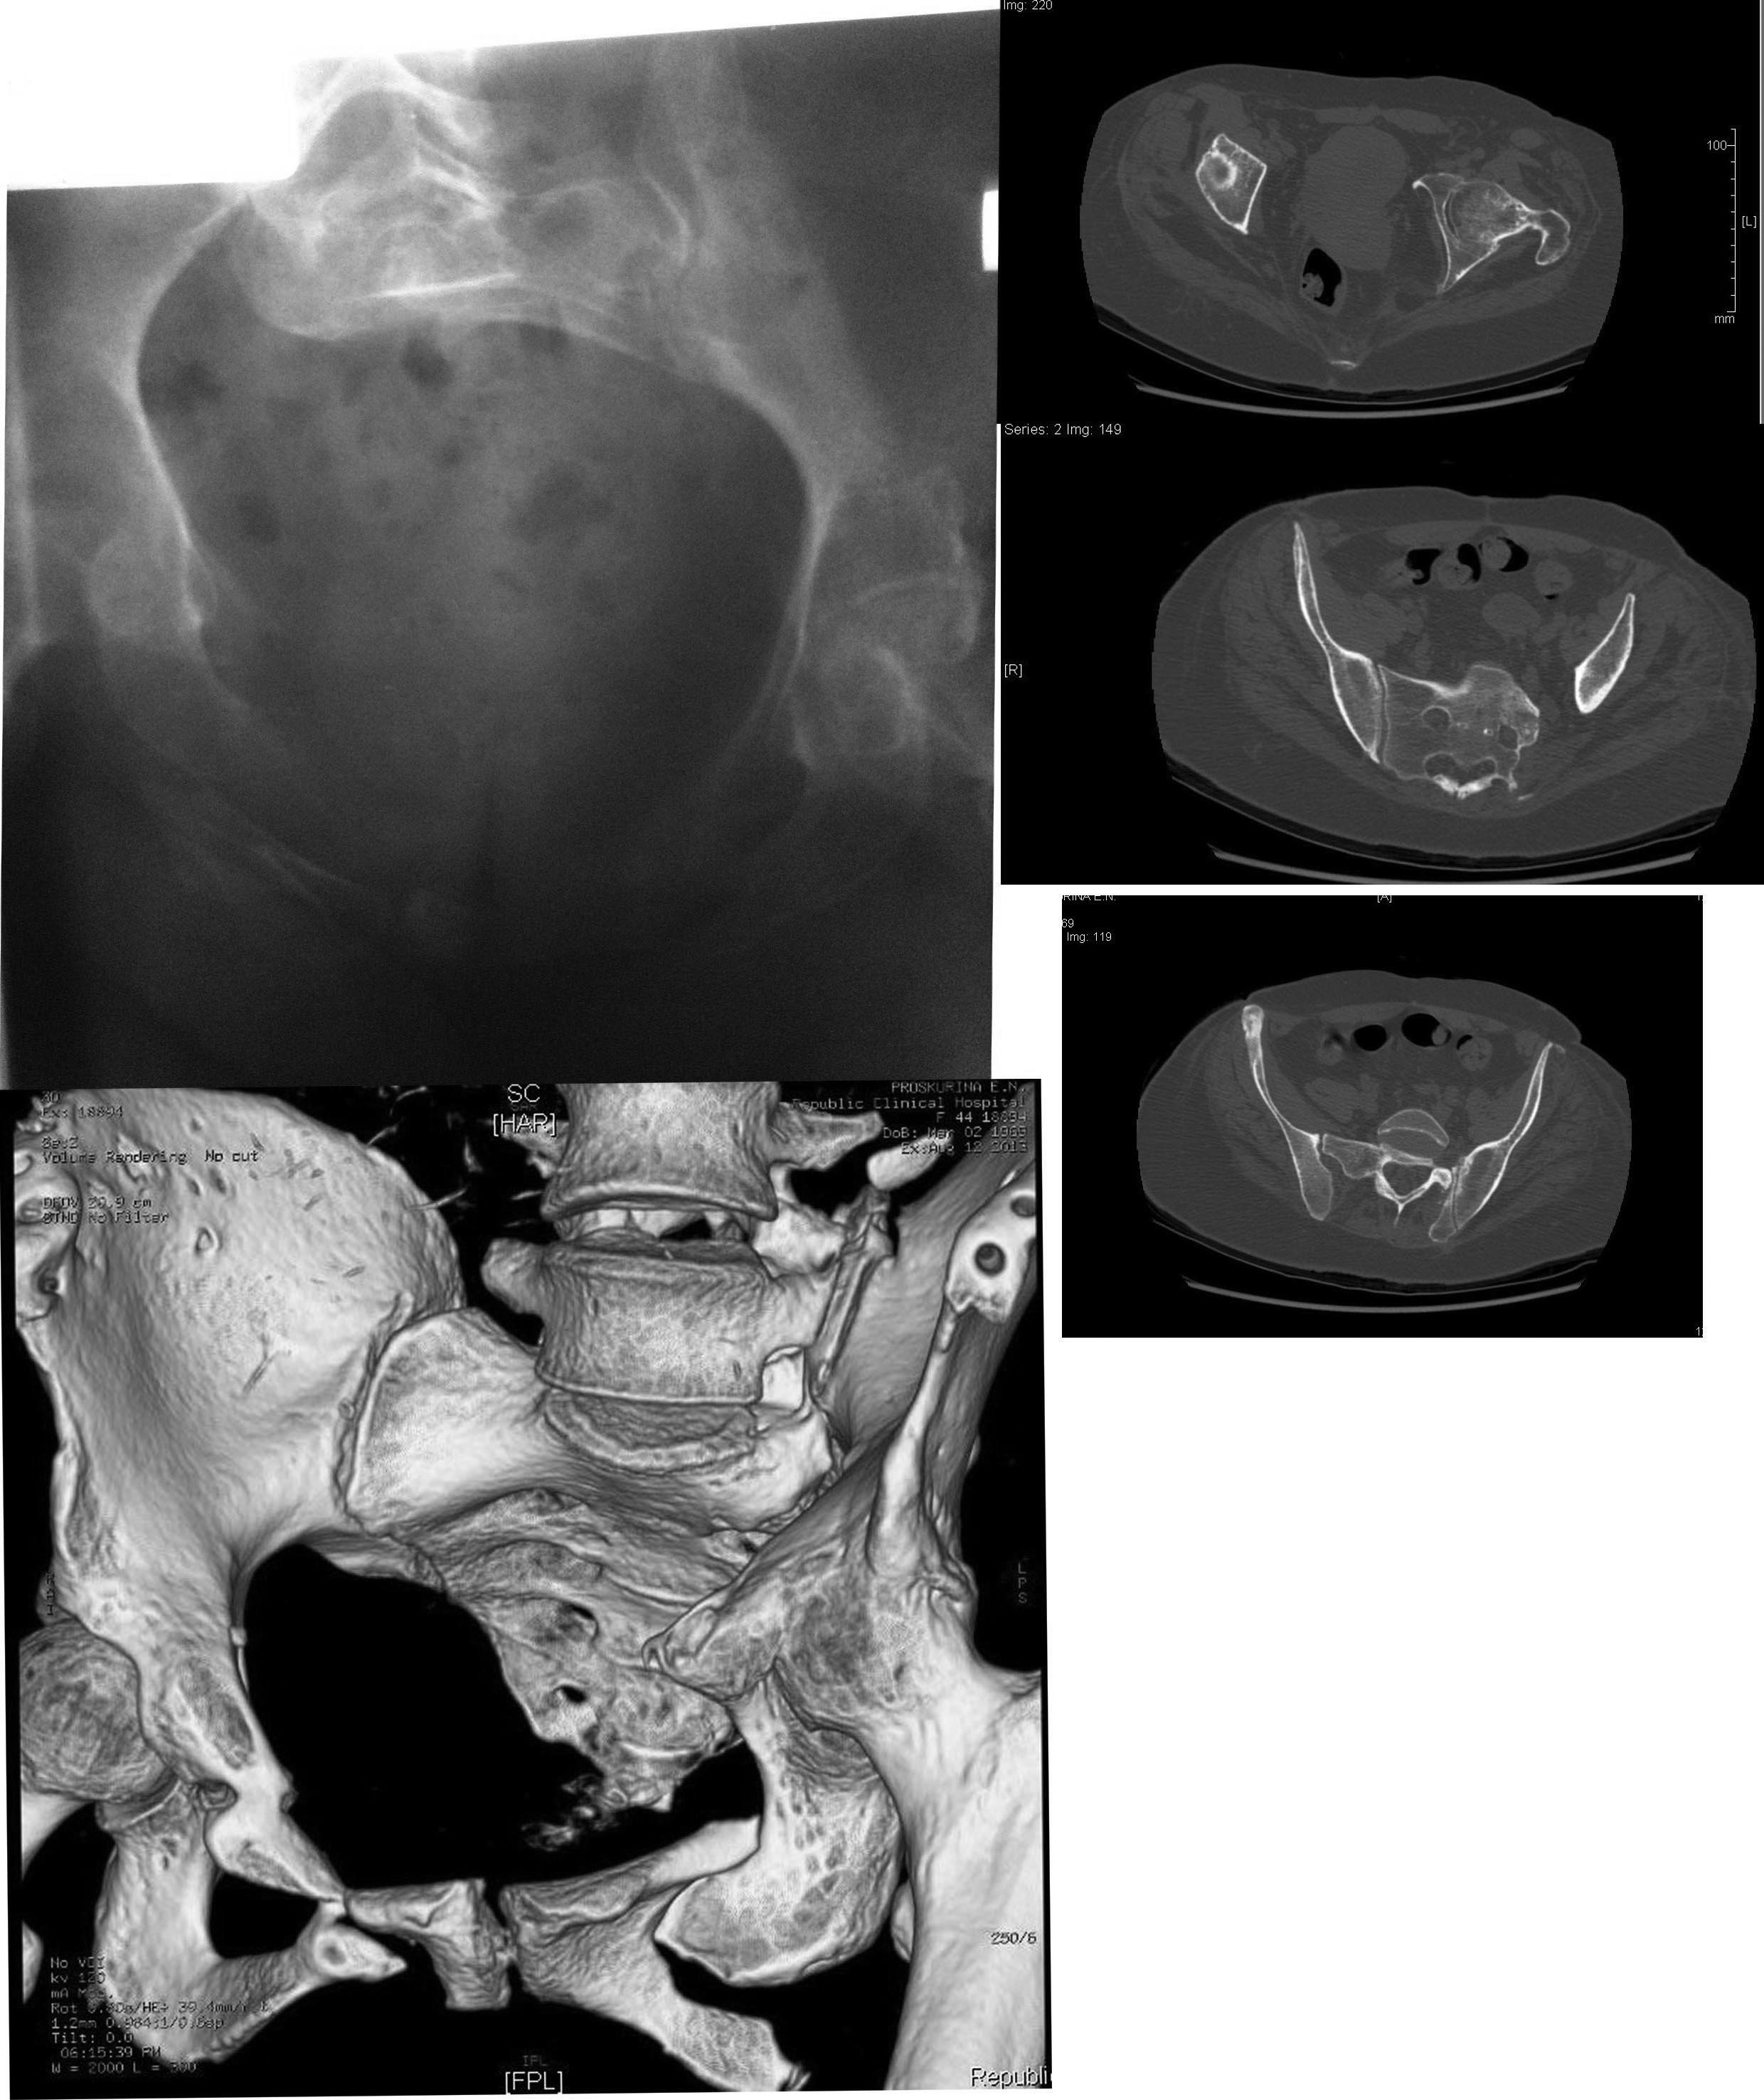

Пациентка П. 44г., травма в 2011г автодорожная Пациентка П. 44г., травма в 2011г автодорожная. Первично - доставлена в областную клинику, где после соответствующего противошокового лечения (лапоротомия по по поводу разрыва мочевого пузыря) применен АВФ, который "носила" 6 месяцев. После демонтажа перелом не сросся. В 2012г по квоте в Кургане вновь о/синтез АВФ. Прошло 11 месяцев, неделю назад аппарат демонтирован. На сегодня передвигается только с помощью костылей, беспокоят боли в левом крестцово-подвздошном сочленении. Клинически: левая нога укорочена на 5см, подвижность в левом т/бедренном суставе отсутствует, тугая подвижность в левом крестцово-подвздошном сочленении. На Rx таза нет сращения переднего полукольца и тугой л/сустав крестца слева, анкилоз левого т/бедренного сустава. Учитывая молодой возраст думаю, что пациентку можно поставить на ноги. Что делать?

ещё рентгенограмма и КТ

Добрый день! Коллеги. Судя по представленным рентгенограммам, имеет место быть унилатеральная вертикальная нестабильная деформация таза III ст. по классификации УНИИТО. Помимо укорочения, боли и анкилозов должны быть урологические проблемы. Интересно былобы узнать оценку урологического статуса. Что касаемо лечения данной проблемой еще занимаются, по мере удаления от столицы: проф. Лазарев (Москва),проф. Казанцев (Москва),д-р Тер-Григорян (Москва), д-р.Донченко (Москва), д-р. Гильфанов (Ярославль),д-р Рунков, д-р Миронов (Томск)и другие. Коллеги извините кого не упомянул мало времени. "На ноги" пациентку поставить можно, желательно совместными усилиями, но процесс лечения будет очень сложным, продолжительным. Это должен понимать лечащий врач и пациент. Успехов Ушаков С.